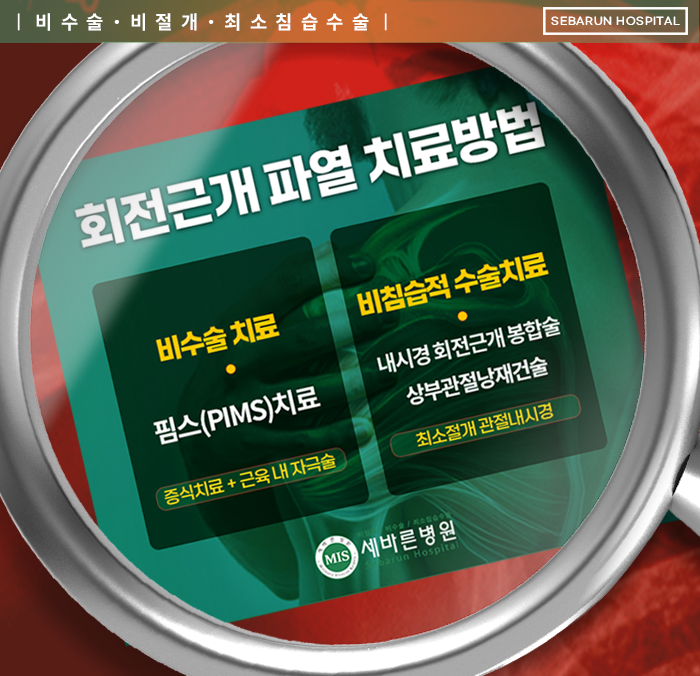

의료기술의 발달로 척추치료와 함께 관절치료에서도 비수술의 비중이 크게 늘고 있는 추세인데요, 그 중에서도 ✔️세바른병원의 어깨 비수술 특화치료 핌스(PIMS)는 회전근개파열, 오십견, 석회화건염, 어깨충돌증후군 등 어깨질환에 폭넓게 활용이 가능한 비수술 치료입니다. 핌스는 크게 두 가지 과정으로 나뉘는데요, 첫 번째는 프롤로테라피(증식치료)인데, 조직 재생을 유도하는 약물을 주사하여 관절에 생긴 염증이나 유착 등을 치료하는 것입니다. 이후에는 노화를 거치며 수축한 근육을 특수 바늘로 자극하여 풀어주는 FIMS(기능적 근육내 자극치료)를 시행하는데, 이는 근육을 충분히 이완시켜 관절 운동을 원활하게 하도록 돕는 것에 목적이 있습니다.

회전근개파열이 미약하게 발생했다면 비수술 치료로도 호전을 기대할 수 있지만, 회전근개 완전파열의 경우에는 수술적 치료를 진행하게 됩니다. 파열된 어깨 회전근개가 범위가 넓거나 증상이 심한 경우, 혹은 이미 회전근개봉합술로 회전근개파열 치료를 했는데도 추후 재파열이 되어 어깨 재수술을 해야 하는 경우에는 봉합이 어려울 정도로 심하게 파열된 경우도 있습니다.

이제는 의료기술의 발달, 첨단 의료기기의 보급으로 인해 회전근개 재파열 또는 어깨힘줄이 완전히 다 끊어져서 팔을 못 들어 올리는 환자분들도 ⭐마지막 단계인 인공관절 수술을 하지 않고도 내시경을 이용하여 자기의 관절을 그대로 사용할 수 있는 치료방법이 고안되었습니다. 바로✅상부관절낭재건술이라고 하는 방법인데요. 지금부터 알아보겠습니다.

어깨 힘줄 재파열, 인공관절 대신 상부관절낭재건술(SCR) 치료

회전근개파열을 늦게 진단받았거나 일반 회전근개 봉합술 적응증이 안 되는 경우, 어깨 재수술을 해야 하는 경우에 시도할 수 있는

어깨 치료방법으로 세바른병원의 상부관절낭재건술 치료방법이 있는데요, 비어있는 회전근개 범위가 커서 봉합술이 불가능하다 판단될 경우에도 서초동 정형외과 세바른병원의 상부관절낭재건술을 통해 동종진피,인조인대를 사용하여 비어있는 회전근개 부위를 재건할 수 있습니다.